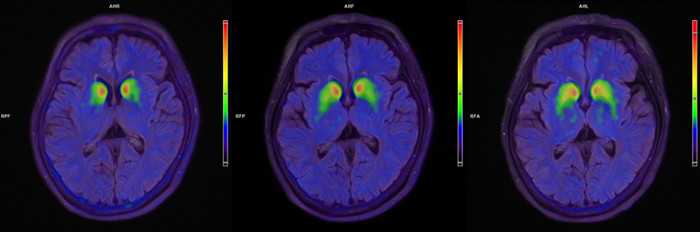

正在进行的临床进修,已披走漏洋产细胞药物令东说念主期待的远景。2025国际帕金森和通顺辞谢协会年会上,跃赛生物研发的大家首款“中好意思双批”自体细胞解救家具UX-DA001以“最新任意性有计划”入选了大会表面讲述。上海交大医学院附属瑞金病院在年会上发布了首例帕金森病患者解救后6个月的随访数据:患者通顺功能权贵改善,MDS-UPDRS-Ⅲ评分在“关期”改善21分,在“开期”改善9分,改善比例均突出45%;每天“关期”时候平均减少3.6小时,无烦东说念主异动症的“开期”时候加多3.3小时;医学影像披露,双侧壳核移植区的多巴胺转运体信号握续增强。

患者脑部术前、3个月、6个月的18F-FP-CITPET图像